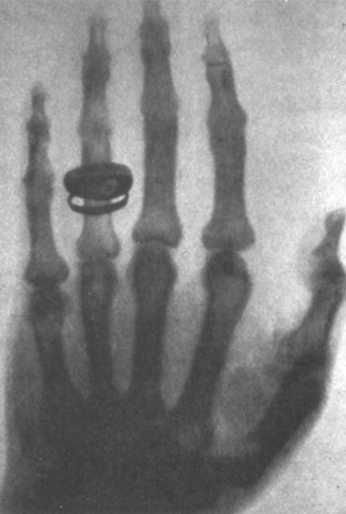

![]() Облученные коротковолновым ультрафиолетовым (УФ) излучением, урановый шар слева — флуоресцентный, кальцит — фосфоресцентный. ИОНИЗАЦИЯ И РЕНТГЕНОВСКИЕ ЛУЧИ Когда появилось известие об открытии рентгеновских лучей, Томсон принял решение немедленно приступить к их изучению и предложил своему ассистенту помочь ему в этом деле. В мае 1896 года Резерфорд написал будущей жене о новом направлении исследований: "Томсон был очень занят изучением нового способа фотографирования, открытого Рентгеном [...]. Профессор пытается открыть истинную причину возникновения и природу волн, его цель — прежде других разобраться в теории материи, так как сейчас все исследователи Европы начали войну с этой проблемой". В 1896 году Резерфорд и Томсон представили научному сообществу данные о том, что рентгеновские лучи ионизировали газы, то есть газ оказывался лучшим проводником электричества при рентгеновском облучении. Это свойство, которое начали использовать для идентификации рентгеновских лучей, было характерно и для других видов излучения, поэтому предположили, что рентгеновские лучи могли оказаться одним из видов электромагнитного излучения. Немецкий физик Макс фон Лауэ (1879-1960) смог подтвердить эту гипотезу спустя два десятилетия. Томсон отдавал все силы исследованиям катодных лучей, и его работу венчало открытие: катодные лучи оказались отрицательно заряженными частицами, поток которых возникал из атомов. Сразу после этого открытия Томсон предложил свою модель атома. Пока Томсон изучал атом, Резерфорд исследовал ионизацию газов другими видами излучения, в том числе ультрафиолетовым. Также он решил заняться и рентгеновскими лучами, сразу после того как пришли новости об их открытии. Но не одного его привлекло открытие Беккереля. В Париже супружеская чета Кюри также очень заинтересовалась им. Резерфорд и Кюри разделяли одни и те же научные интересы, что привело их не только к сотрудничеству, но и к соперничеству. ![]() Студенты Кавендишской лаборатории, 1898 год. В центре первого ряда (со скрещенными руками) Дж. Дж. Томсон; во втором ряду четвертый слева — Резерфорд. ![]() Первая радиография Рентгена, на которой мы видим руку его жены Берты. ![]() Немецкий физик Вильгельм Конрад Рентген. РАДИОАКТИВНОСТЬ И КЮРИ Мария Склодовская (1867-1934) родилась в Варшаве. Чтобы поступить в университет (в Польше женщинам учиться не дозволялось), ей пришлось эмигрировать во Францию, где она стала первой женщиной, получившей степень доктора физики в Сорбонне. Выйдя замуж за ученого, Пьера Кюри, она взяла его фамилию. Раздумывая над темой диссертации, Мария остановила свой выбор на излучении урана, открытого Беккерелем. В качестве детектора лучей тот использовал фотопластинки, что было удобно, однако не позволяло количественно измерить интенсивность радиации. МАРИЯ КЮРИ Младшая из пяти сестер, Мария Кюри родилась в Варшаве в 1867 году и впоследствии приняла французское гражданство. Она стала первой женщиной, получившей докторскую степень во Франции и Нобелевскую премию, и вошла в историю как первый человек, удостоившийся этой награды дважды. Ее отец был преподавателем математики и физики, и с детства Мария выделялась успехами в учебе. В юности ей пришлось много работать, чтобы одна из ее сестер могла поехать в Париж изучать медицину, и был уговор, что сестра потом вернет ей долг. В 1891 году Марии наконец удалось попасть в Сорбонну, где она стала лучшей студенткой своего потока, несмотря на постоянные материальные затруднения. Она получила диплом на кафедре физики в 1893 году, а через год — на кафедре математики. Затем она приступила к лабораторным исследованиям и познакомилась со своим будущим мужем, Пьером Кюри. Их свадьба в 1895 году была скромной. ![]() Мария Кюри, 1920 год. Но вскоре началась успешная работа в тандеме. Несмотря на их увлеченность исследованиями, у четы родились две дочери, Ирен и Ева, в 1897 и 1904 годах соответственно. В 1898 году ученые открыли полоний, затем радий, а также установили радиоактивность тория. Задача по вычислению атомного веса радия потребовала использования тонн урановой смолки. В опытах Кюри задействовали опасные кислоты для растворения металла в больших резервуарах, эти процессы развивались в течение нескольких лет, и сами исследователи вдыхали ядовитые пары. В 1903 году Беккерель, Пьер и Мария Кюри получили Нобелевскую премию по физике за открытие радиоактивности. Неожиданный поворот Внезапная гибель Пьера в 1906 году — он попал под колеса телеги — определила поворот в карьере его жены. Мария, которая могла рассчитывать лишь на должность школьной учительницы, отказалась от предложенной правительством пенсии вдовы, но потребовала отдать ей пост, который занимал в университете ее муж. Так она стала первой женщиной, возглавившей кафедру в высшем учебном заведении. В 1911 году она вновь получила Нобелевскую премию, на этот раз в области химии, за выделение радия. Когда вспыхнула Первая мировая война, Мария и ее дочь Ирен принялись за разработку технологии радиографии и применения ее в лечении раненых. Впоследствии в 1935 году Ирен также удостоилась Нобелевской премии по химии. Мария продолжала поиски медицинского применения своих открытий и умерла 4 июля 1934 года, а в 1995 году в знак почтения перед научными заслугами ученого ее прах был захоронен в парижском Пантеоне. В связи с этим Мария и Пьер Кюри решили обратиться к другому способу, основанному на электрических свойствах излучения, что должно было позволить определить его количество. Резерфорд избрал сходный метод. Выполняя измерения, Мария адаптировала для своих целей электрометр — более точный, чем изобретенный ее мужем электроскоп. Пьер использовал пьезоэлектрический эффект кварцевых стекол (материал своей кристаллической структурой демонстрирует зависимость электрических свойств от механического давления, сжатия/расширения) для создания более чувствительного аппарата. Так как уран ионизировал газы до разной степени электрической проводимости, электрометр из пьезоэлектрического кварца помогал обнаруживать минимальную разницу электрического заряда, индуцированного газами. Мы не должны забывать следующее: когда был открыт радий, никто не знал, что он окажется полезным в медицине. Велись чисто научные исследования. Это доказывает, что научную работу нельзя оценивать лишь с точки зрения ее прикладного значения. Исследования должны проводиться ради красоты науки... |